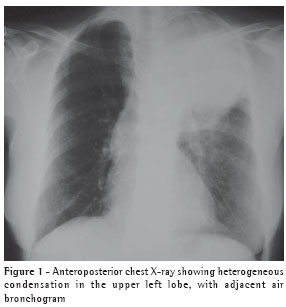

The chest X-ray revealed a dense mass in the upper left lobe (Figure 1).

The computed tomography scan of the chest (Figure 2) confirmed the presence of a heterogeneous mass in the left upper lobe, with air bronchogram adjacent to the mass, suggesting an expansive neoplastic lesion. The patient was unable to produce a sputum sample for testing.

There is no characteristic radiological profile, although the presence of single or multiple nodules that are well defined and not calcified is more common and can mimic neoplasia on the X-ray.(5,9) Radiographic alterations have been reported, including infiltrates (62%), nodules (38%), masses (19%), cavitations (14%) and pleural effusion (3%), without anatomical distribution patterns and without any accompanying hilar or mediastinal lymph node enlargement. Empyema, pneumothorax and pleural involvement suggestive of Pancoast tumor,(13) as well as lung masses invading the chest wall,(14) have also been reported in the literature. A computed tomography scan of the chest corroborates the radiological findings, providing better details for the differential diagnosis,(11) and, when necessary, helps program the invasive diagnostic techniques. In the present case, the patient presented a lung mass that mimicked neoplasia.